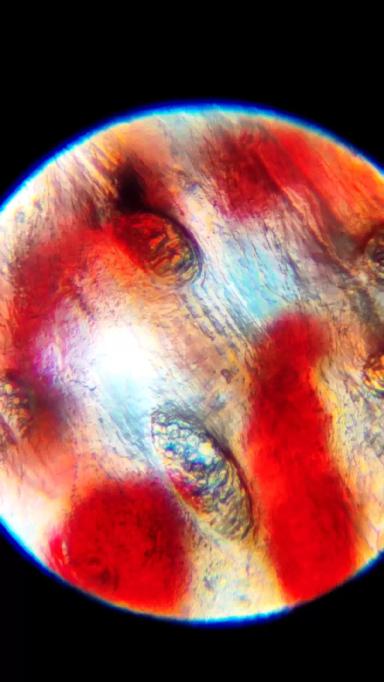

Кровоизлияние в подошве копытца у коровы

При функциональной и терапевтической обрезки копытец у коров, можно наблюдать такую патологию как кровоизлияние в подошве. Есть несколько факторов образования ее, но я хочу рассмотреть в данной статье одну ...